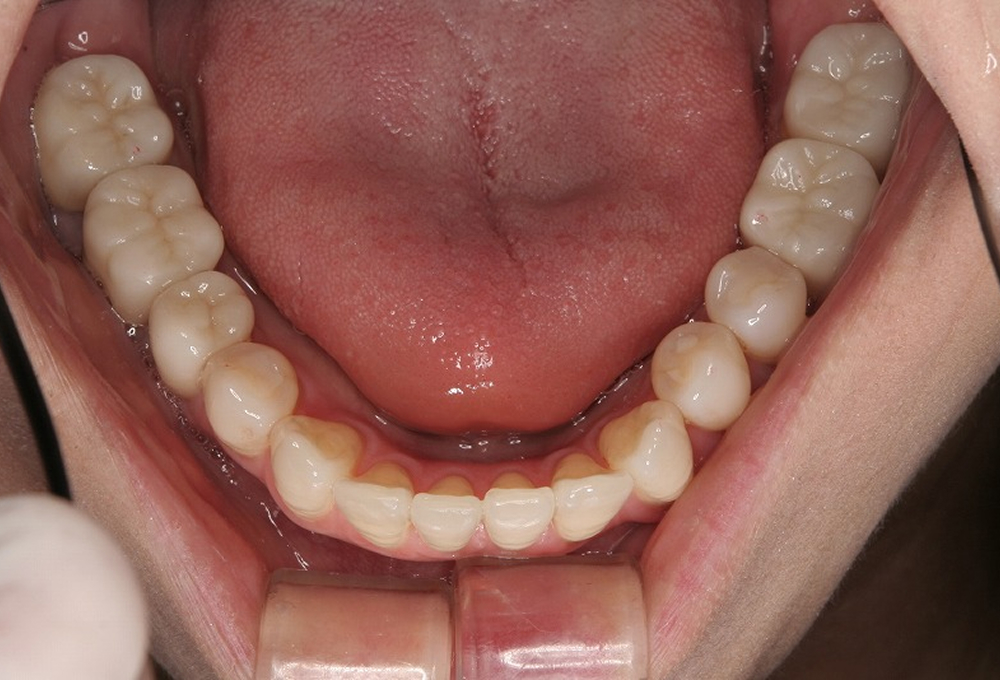

⑤拡大床後、6前歯のみ約3ヶ月ブラケットを装着し矯正

⑥ブラケットをはずし矯正終了。綺麗な歯並びになりました